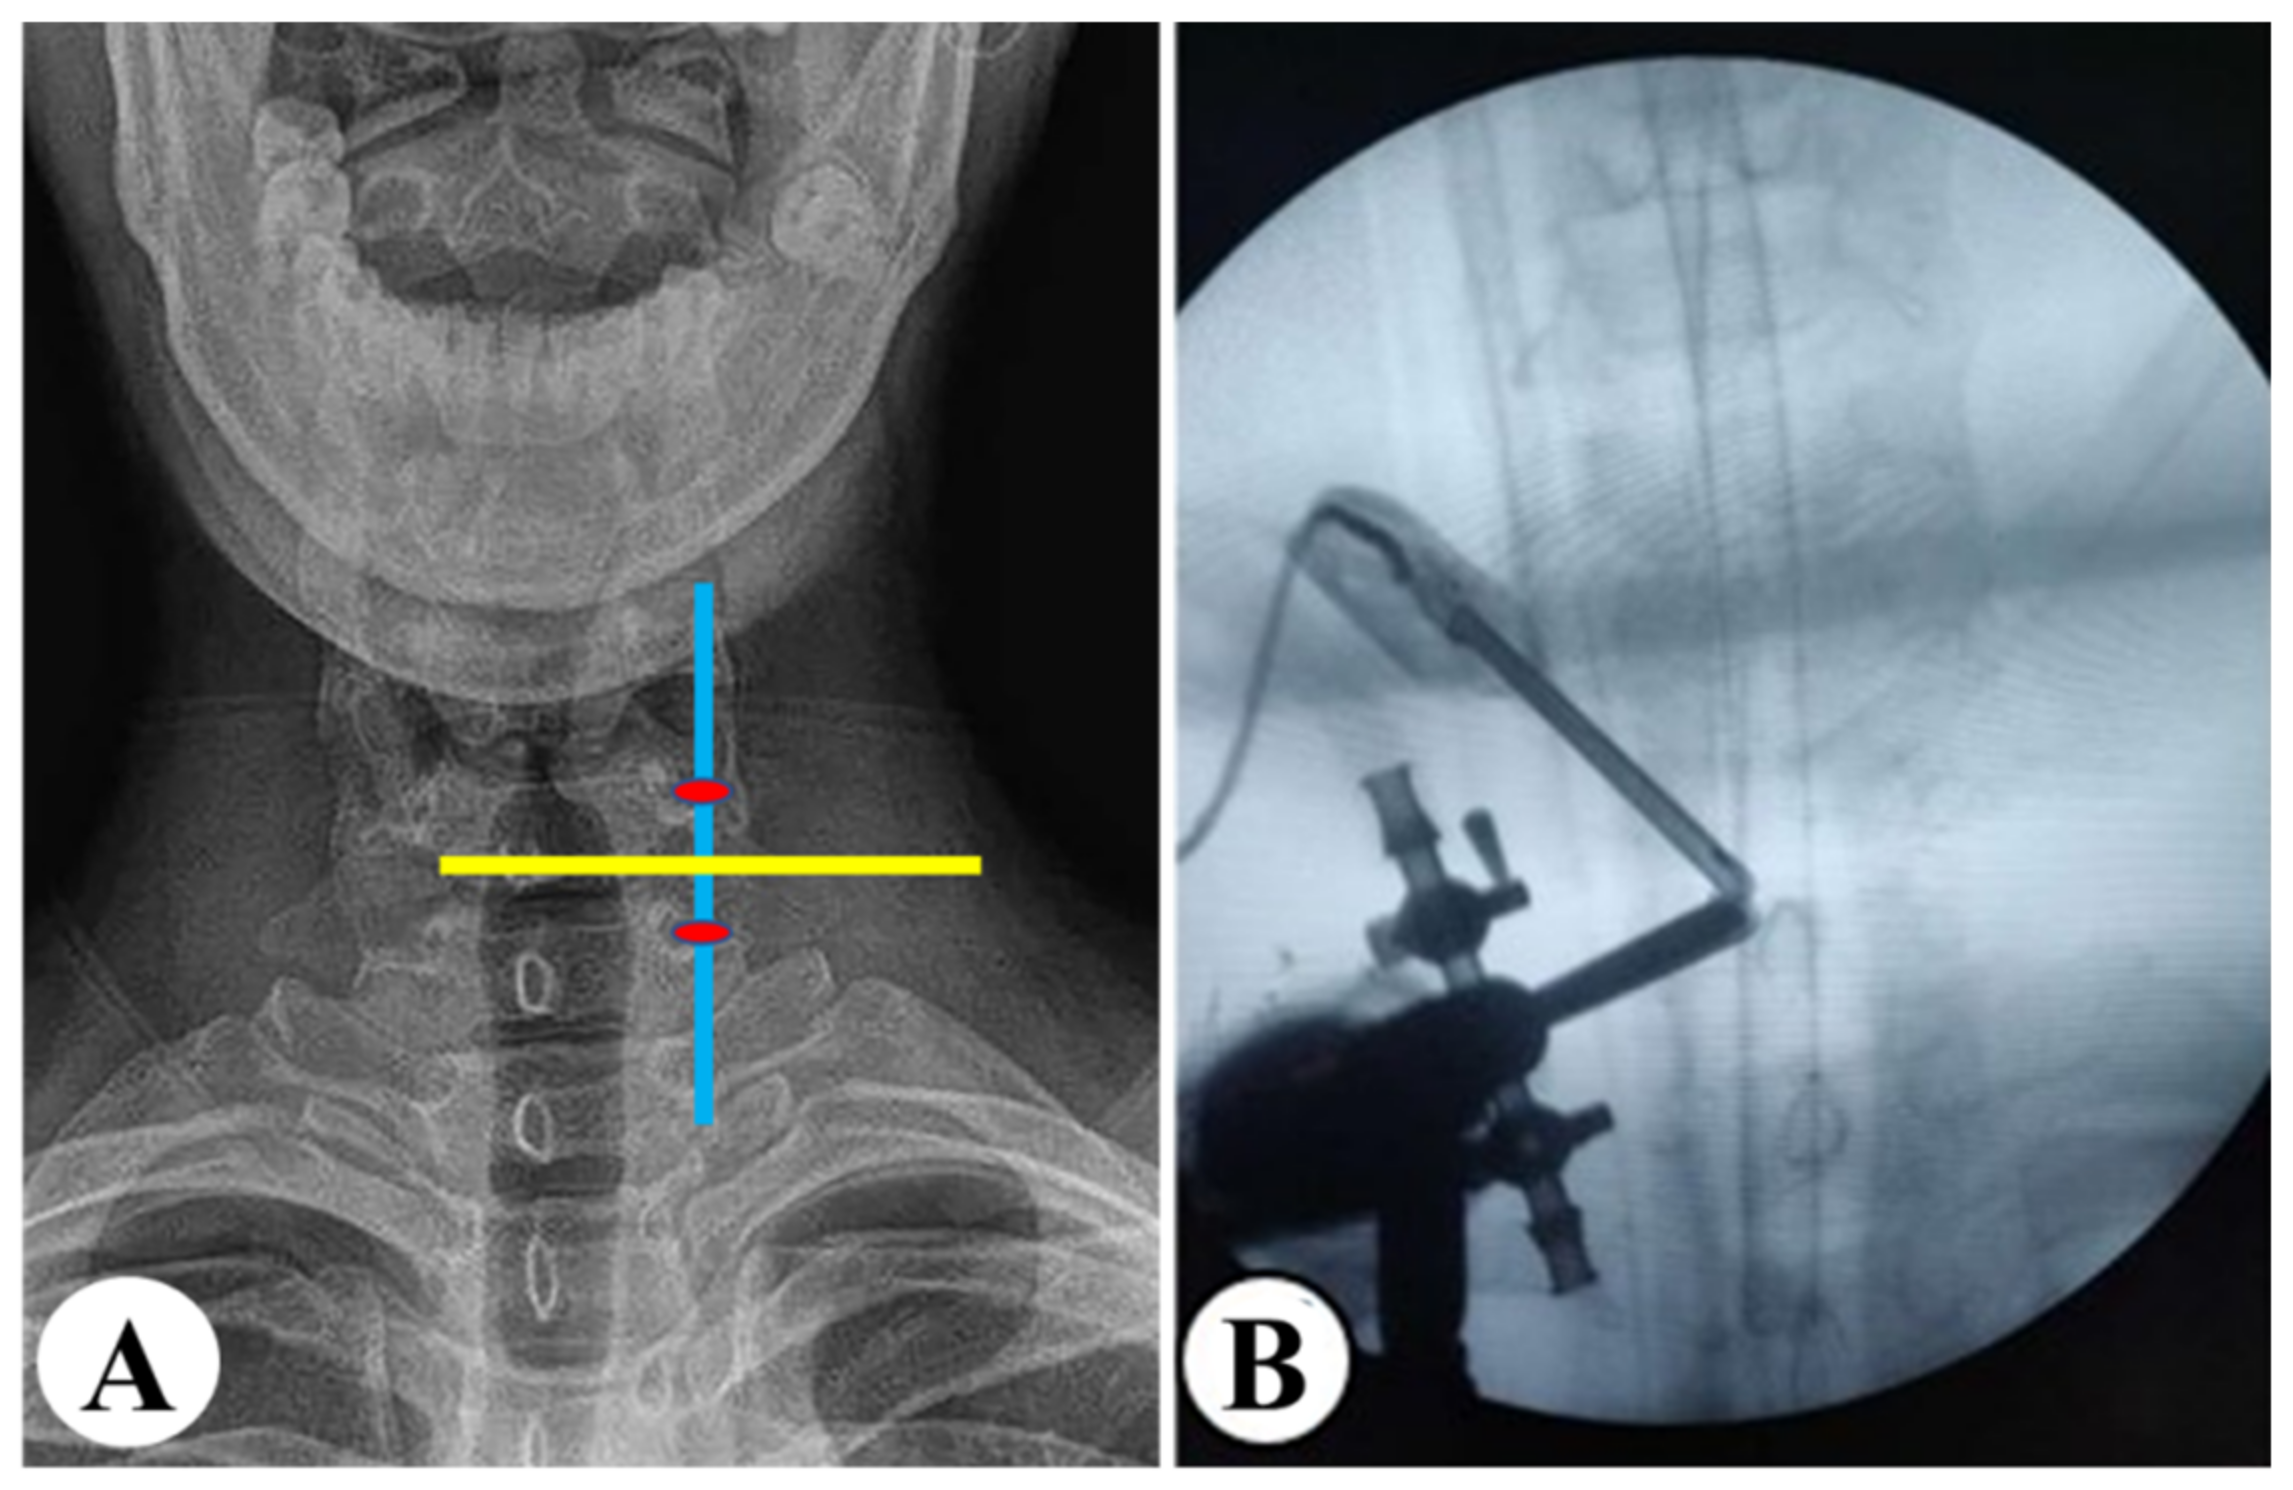

2.4.2. Radiological Measurement

| Before | 12 Months After Surgery | Last Follow-Up | F | p | |

| C2-7 Cobb’s angle (°) | |||||

| UBE | 16.87 ± 2.89 *,† | 23.41 ± 4.04 * | 24.46 ± 3.94 † | 97.527 | <0.001 |

| PE | 16.66 ± 2.70 *,† | 22.38 ± 5.73 * | 23.53 ± 6.02 † | 39.525 | <0.001 |

| C2-7 ROM (°) | |||||

| UBE | 22.60 ± 7.59 *,† | 24.58 ± 9.58 *,‡ | 27.57 ± 9.45 †,‡ | 6.997 | 0.001 |

| PE | 22.08 ± 8.23 *,† | 25.71 ± 8.17 * | 26.42 ± 9.62 † | 4.500 | 0.013 |

| Intervertebral height of the surgical segment (mm) | |||||

| UBE | 5.51 ± 0.38 | 5.43 ± 0.42 | 5.52 ± 0.40 | 1.202 | 0.303 |

| PE | 5.42 ± 0.37 * | 5.61 ± 0.37 * | 5.56 ± 0.40 | 1.865 | 0.159 |

| Vertebral horizontal displacement of the surgical segment (mm) | |||||

| UBE | 1.24 ± 0.28 | 1.25 ± 0.29 | 1.32 ± 0.24 | 1.960 | 0.144 |

| PE | 1.21 ± 0.29 | 1.26 ± 0.29 | 1.20 ± 0.26 | 0.897 | 0.410 |

| Vertebral angular displacement of the surgical segment (°) | |||||

| UBE | 5.39 ± 1.16 | 5.55 ± 1.25 | 5.66 ± 1.20 | 1.276 | 0.282 |

| PE | 5.27 ± 1.34 | 5.39 ± 1.32 | 5.29 ± 1.29 | 0.125 | 0.883 |